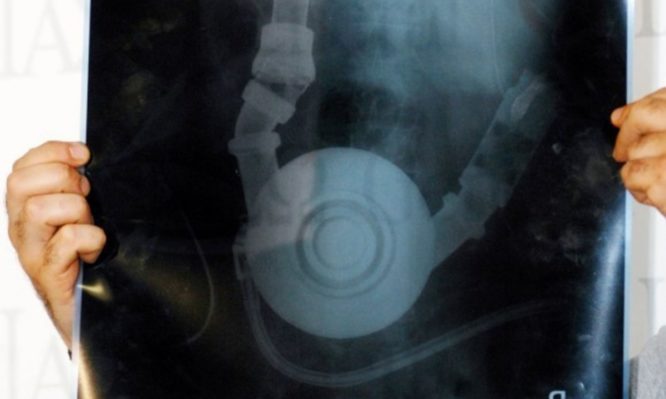

Ηράκλειο: Είδαν τις εξετάσεις του 8χρονου Μάνου και έμειναν άφωνοι – Το λάθος και η ανατροπή!

Ο 8χρονος Μάνος μεταφέρθηκε σε νοσοκομείο του Λονδίνου - Οι γιατροί τον υπέβαλαν σε μια σειρά εξετάσεων και ύστερα από λίγες ώρες πήραν τα αποτελέσματα...